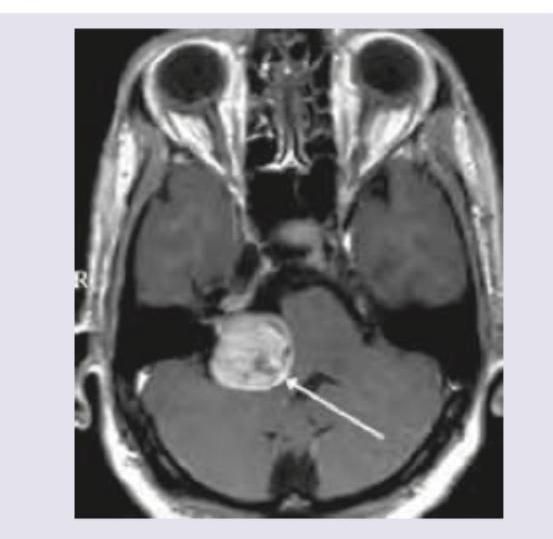

Question 6: MRI Brain of a 40-year-old patient with progressive unilateral SNHL and tinnitus is shown below. Which is the most common extracanalicular nerve to be involved?

- A. V (Correct Answer)

- B. VI

- C. VII

- D. VIII

Explanation: ***V*** - The image shows a large **right cerebellopontine angle (CPA) mass**, consistent with an **acoustic neuroma** (vestibular schwannoma), which commonly arises from CN VIII in the internal auditory canal and extends into the CPA. - The **trigeminal nerve (CN V)** is the most common extracanalicular cranial nerve to be compressed and involved by larger CPA tumors due to its proximity and superior-anterior position relative to CN VIII. *VI* - The abducens nerve (CN VI) controls the lateral rectus muscle of the eye, and its involvement typically causes **diplopia** and **lateral gaze palsy**. While possible with very large and medially extending CPA tumors, it is less common than CN V involvement. - CN VI is located more medially and anteriorly within the brainstem and generally requires significant mass effect rather than direct compression from a typical CPA tumor. *VII* - The facial nerve (CN VII) travels with the vestibulocochlear nerve (CN VIII) through the **internal auditory canal**, and is frequently involved by acoustic neuromas within the canal, leading to **facial weakness or paralysis**. - However, the question specifically asks for the most common **extracanalicular** nerve involvement. While CN VII is intimately associated, its most common site of involvement is within the canal, or early in the CPA, and V is often implicated with larger CPA masses. *VIII* - The vestibulocochlear nerve (CN VIII) is the nerve from which **acoustic neuromas (vestibular schwannomas)** originate, causing the presenting symptoms of **unilateral SNHL and tinnitus**. Therefore, it is the primary affected nerve, not an extracanalicular one involved due to compression. - The question asks for the most common **extracanalicular nerve to be involved**, implying a nerve *other than* the one the tumor originates from or primarily affects locally within the canal.